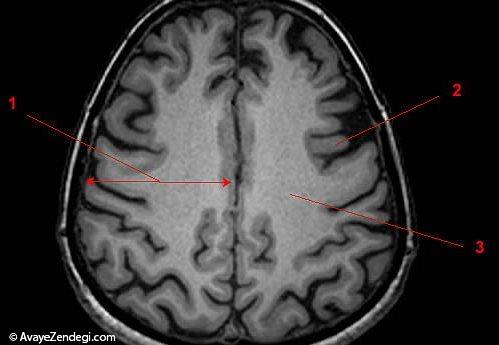

2- در سمت چپ مغز، 200 میلیون نورون بیشتر از سمت راست مغز وجود دارد.

5- موضوعات بحث برانگیز مربوط به جنسیت در مغز؛ با توجه به بررسی های انجام شده در سال 2014، مقدار بیشتری از ماده خاکستری در مغز زنان موجود است.

6- ماده خاکستری مربوط به مهارت های زبان می شود و بسیار پیشرفته است.

8- اطلاعاتی جالب؛ ماده خاکستری که 40٪ مغز را تشکیل می دهد، تنها پس از مرگ، به رنگ خاکستری در می آید.

10- مقدار ماده سفید در مغز مردان بیشتر است و تصور می شود این ماده، مایع مغزی نخاعی است.